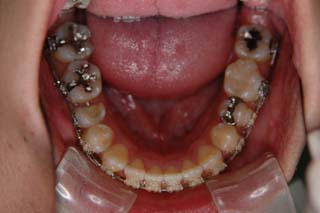

次第にアゴのズレが取り除かれて、しっくり噛めるかみ合わせに変化していっています。長い年月をかけて修飾されてきた顎関節の環境はなかなか良い形に変わりませんので、時間をかけて改善を行います。